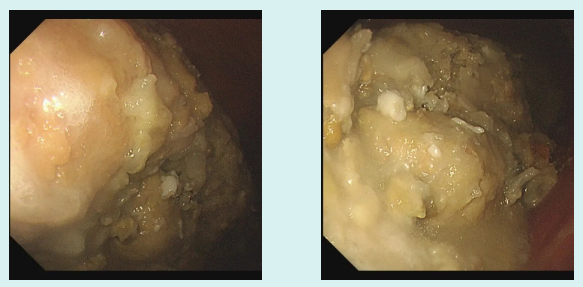

接诊的吕主任详细询问病史后,初步判断关女士可能因大量食用山楂引发了胃结石。随后的无痛胃镜检查证实了这一猜测——关女士的胃体里有一颗超大结石。

鞣酸会与胃酸、食物中的蛋白质结合,形成不溶于水的沉淀物,这些沉淀物和果胶、食物残渣等缠结在一起,就像滚雪球一样,逐渐形成胃结石。